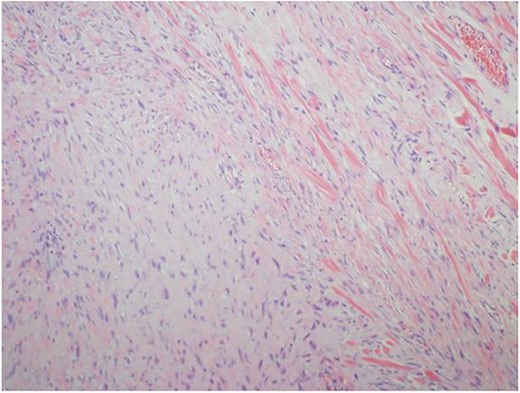

Ultrasound guided biopsy was performed, which showed spindle cells fascicles with collagen formation. The cells were stained positive to beta-catenin nuclear staining, and negative for SMA, CD34, Desmin and S100 (Figs 3 and 4). The diagnosis of desmoid fibromatosis was confirmed.

Histopathological findings. Spindle cells fascicles with collagen formation (H&E ×100).